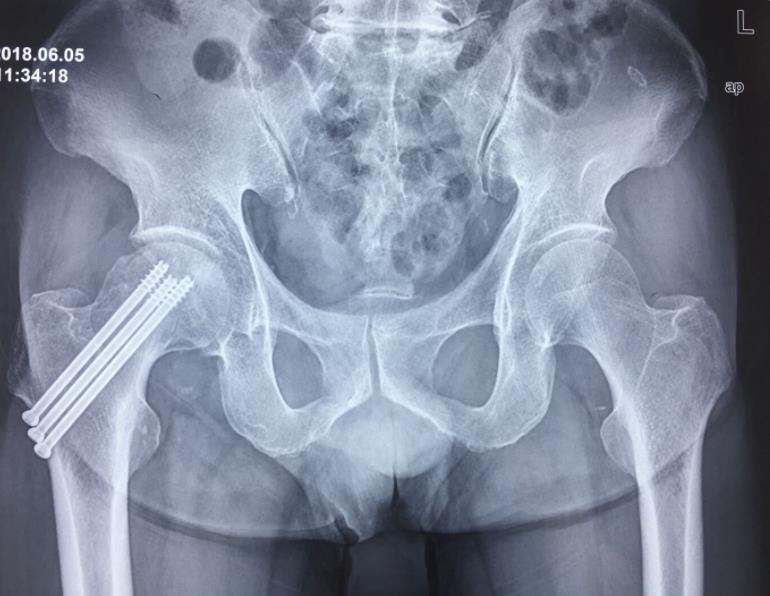

闭合复位经皮固定手术步骤

1、经皮沿股骨颈轴线置入空心钉导针,确保导针平行;

2、标准放置螺钉为倒三角形,其中下方螺钉在股骨矩,后方螺钉在后方骨皮质、研究发现倒三角形平行三枚螺钉能提供最佳的固定强度;

3、螺钉位于股骨颈四周,特别是后侧及下方,避免低于小转子方向进针,可能导致术后转子下骨折;

4、两个平面透视导针位置良好后切开皮肤,空心钻铭孔,导针引导下拧入空心钉,空心钉确保所有螺纹位于骨折线近端,螺钉头应距离软骨下骨5mm。

空心钉固定的三原则:“贴边、平行、倒品”。

1、贴边是指3枚螺钉在股骨颈内,尽量靠近外围皮质。这样3枚螺钉作为一个整体,对整个骨折面可形成面状加压,如果3枚螺钉不够离散,更趋于点状加压,稳定性较差,不能较好地对抗扭转和剪切。

有研究显示,在侧位片上,螺钉的前后分布越分散,骨折不愈合发生率越低。J Bone Joint Surg Br. 2005 May: 87(5): 632-4.

图1 3枚螺钉在股骨颈内的理想位置

图2 倒品字固定

3、平行生物力学更稳定。